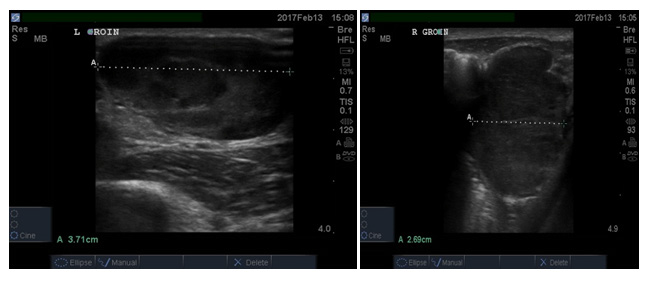

A 22-year-old male consulting Emergency department for voice changes, cough for 1 week, neck swelling extending to the both ears lasting for 4 weeks, peri - orbital swelling, and swelling in both groins (Figure 1). On arrival, he was in respiratory distress, oxygen saturation: 87%, unable to pronounce some letters; as emergency management, he was given oxygen 5L/ min with non retreater mask and saturation: 92-95%.

Figure 1 A 22-year-old male consulting Emergency department for voice changes, cough for 1 week, neck swelling extending to the both ears lasting for 4 weeks, peri - orbital swelling, and swelling in both groins.

The patient had multiple huge adenopathies localized on cervical region, subclavical region, both axillar, and on both groins. Bed site Ultrasound findings: multiple lymph nodes of neck and para-auricular, cervical, axillar, and inguinal regions. The biggest measuring 3-5 cm. He also had huge ascitis, bilateral pleural effusion, and small pericardial effusion. Initial laboratory results were showing mild elevated white blood cell (24.15), with normal differentiation Hemoglobin of 8.3g/dl; renal, liver function test, and electrolytes were normal. The following are bed site ultrasound images (Figures 2-7). Based on history, physical exam and Ultrasound images, we can conclude that swelling is lymph nodes and not anything else. Our differential diagnoses were Hodgikin lymphoma. To rule out TB adenitis, the internal medicine consultant requested a fine needle aspiration (FNA), which was none conclusive, and the pathologist suggested doing an open biopsy. The results of open biopsy showed: HL Hodgkin lymphoma (Nodular sclerosis type). Nodular sclerosis Hodgkin's disease accounts for 80% of all Hodgkin's disease.2

Figure 2 & 3 Left groin big lymph node & Right groin lymph node.